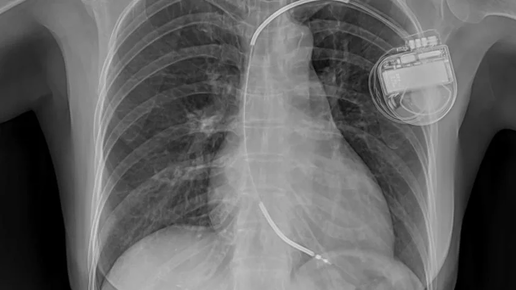

Одно дело, если такая частота сердечных сокращений (скажем, 45-50 в минуту) зарегистрирована на ЭКГ. Несколько другое дело - если на холтеровском мониторе. Синусовый ритм с частотой 45 в минуту на ЭКГ может быть зарегистрирован и у здорового человека, но все-таки 45 - повод насторожиться, а нет ли тут дисфункции синусового узла, или, как говорили еще недавно - синдрома слабости синусового узла. Если частота ритма 45 в минуту регистрируется на ЭКГ у спортсмена, физкультурника или у человека, регулярно...